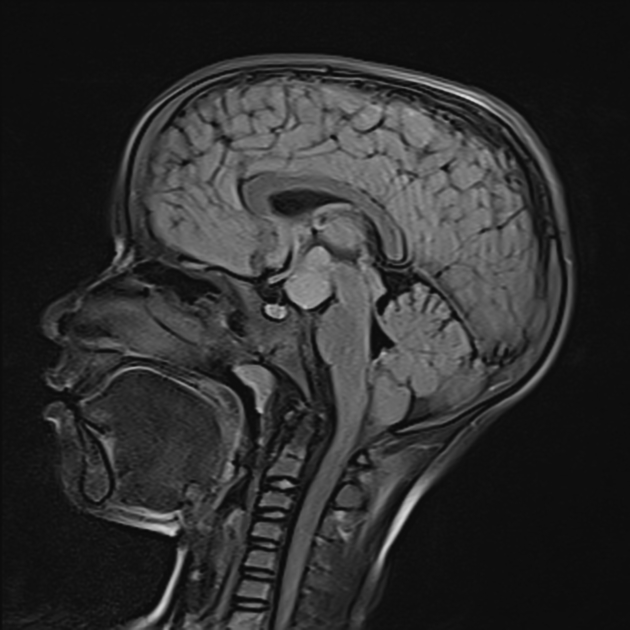

Gelastic seizures, marked by bouts of uncontrollable laughter, are classically linked to hypothalamic hamartomas. They may also be associated with Pallister-Hall syndrome (caused by a GLI3 mutation on chromosome 7). Present in infancy. EEG often normal due to deep seizure focus.